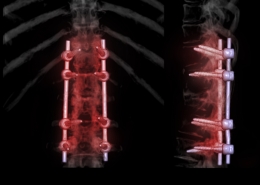

- Scoliosis, kyphosis

- Spinal fracture

- Minimally invasive spine surgery

- Pediatric spinal disorders

- Spinal deformities in adults